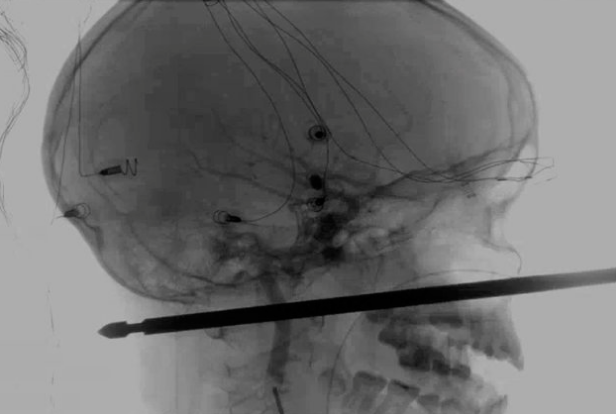

木から転落し、金串が顔を貫通した10歳の少年が病院に運ばれたものの、奇跡的に助かり、現在は回復までに至ったそうです。

アメリカ在住の10歳の少年は遊んでいる最中、スズメバチの攻撃を受け、木から落ちてしまいました。そして運悪く、バーベキュー用の金串が少年の顔を貫通してしまったのです。事故当時、少年の悲鳴を聞いた母親は、裏庭で倒れている息子が「僕、死んじゃうかも」と泣き叫んでいたものの、うまく落ち着かせ近くの病院に運んだといいます。

そこで少年は病院で治療を受けることになりますが、レントゲン写真を見て驚き。少年は痛い思いをしてしまったものの、目、脳、脊髄、大動脈などの重要な部分に全く損傷がみられなかったのです。

事故に遭った少年もこれには驚いているようで「金串で顔が貫通したにもかかわらず急所に刺さらなかったのは奇跡としかいいようがない」と話しています。しかし、手術で金串を除去することはかなり至難の業。少しでも金串が急所に当たってしまうと、傷がもっと悪化する可能性があります。

最終的に手術は大成功。医者でさえも「奇跡」と明かしたくらいで「これだけ深い傷を負って生きている患者を見たことがない。もちろん完治することも難しいはず」とのことですが、この少年は順調に回復しているそうなので、このままいけば完治できるそうです。